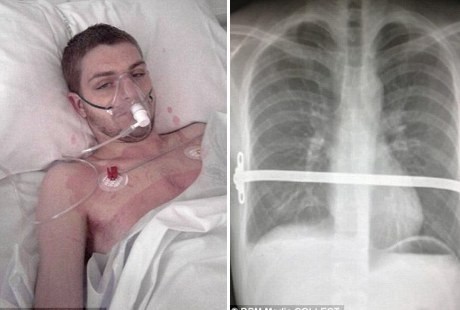

Tulang Rusuk Pria Ini Harus Dipasangi Logam karena Penyakit Langka - detikHealth Jumat, 22 Feb 2013 20:04 WIB dok: Daily Mail Jakarta - (vit/vit) Infografis Lainnya Infografis Feeding Difficulty Vs Picky Eating, Apa Beda & Dampaknya bagi BB Anak? Infografis Waspadai Dampak Picky Eating pada Anak, Berikut Cara Jitu Cegahnya Infografis Infografis: Strategi dan Formasi Ideal untuk Menang Lomba Balap Bakiak